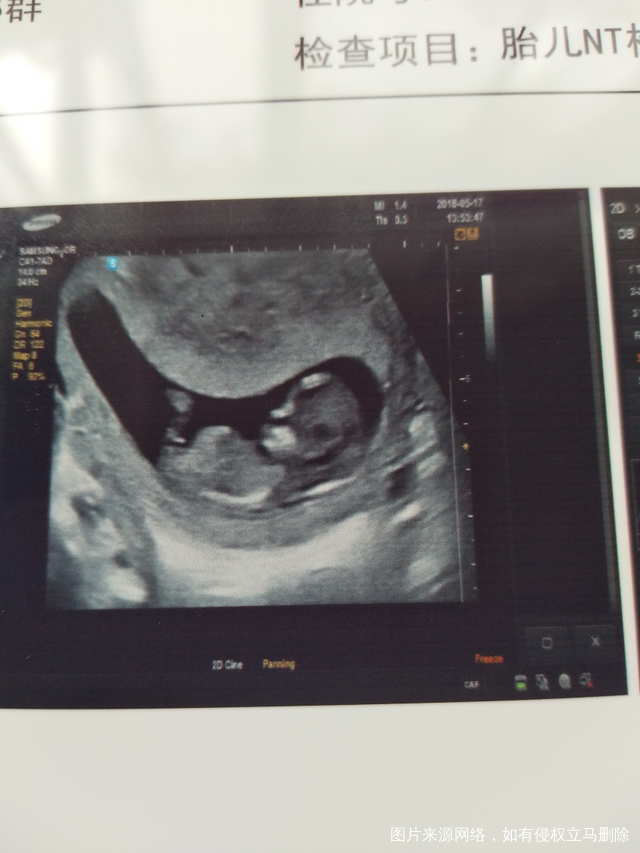

刚刚去医院交单子,然后医生说很正常,孩子也健康太好了😄哈哈